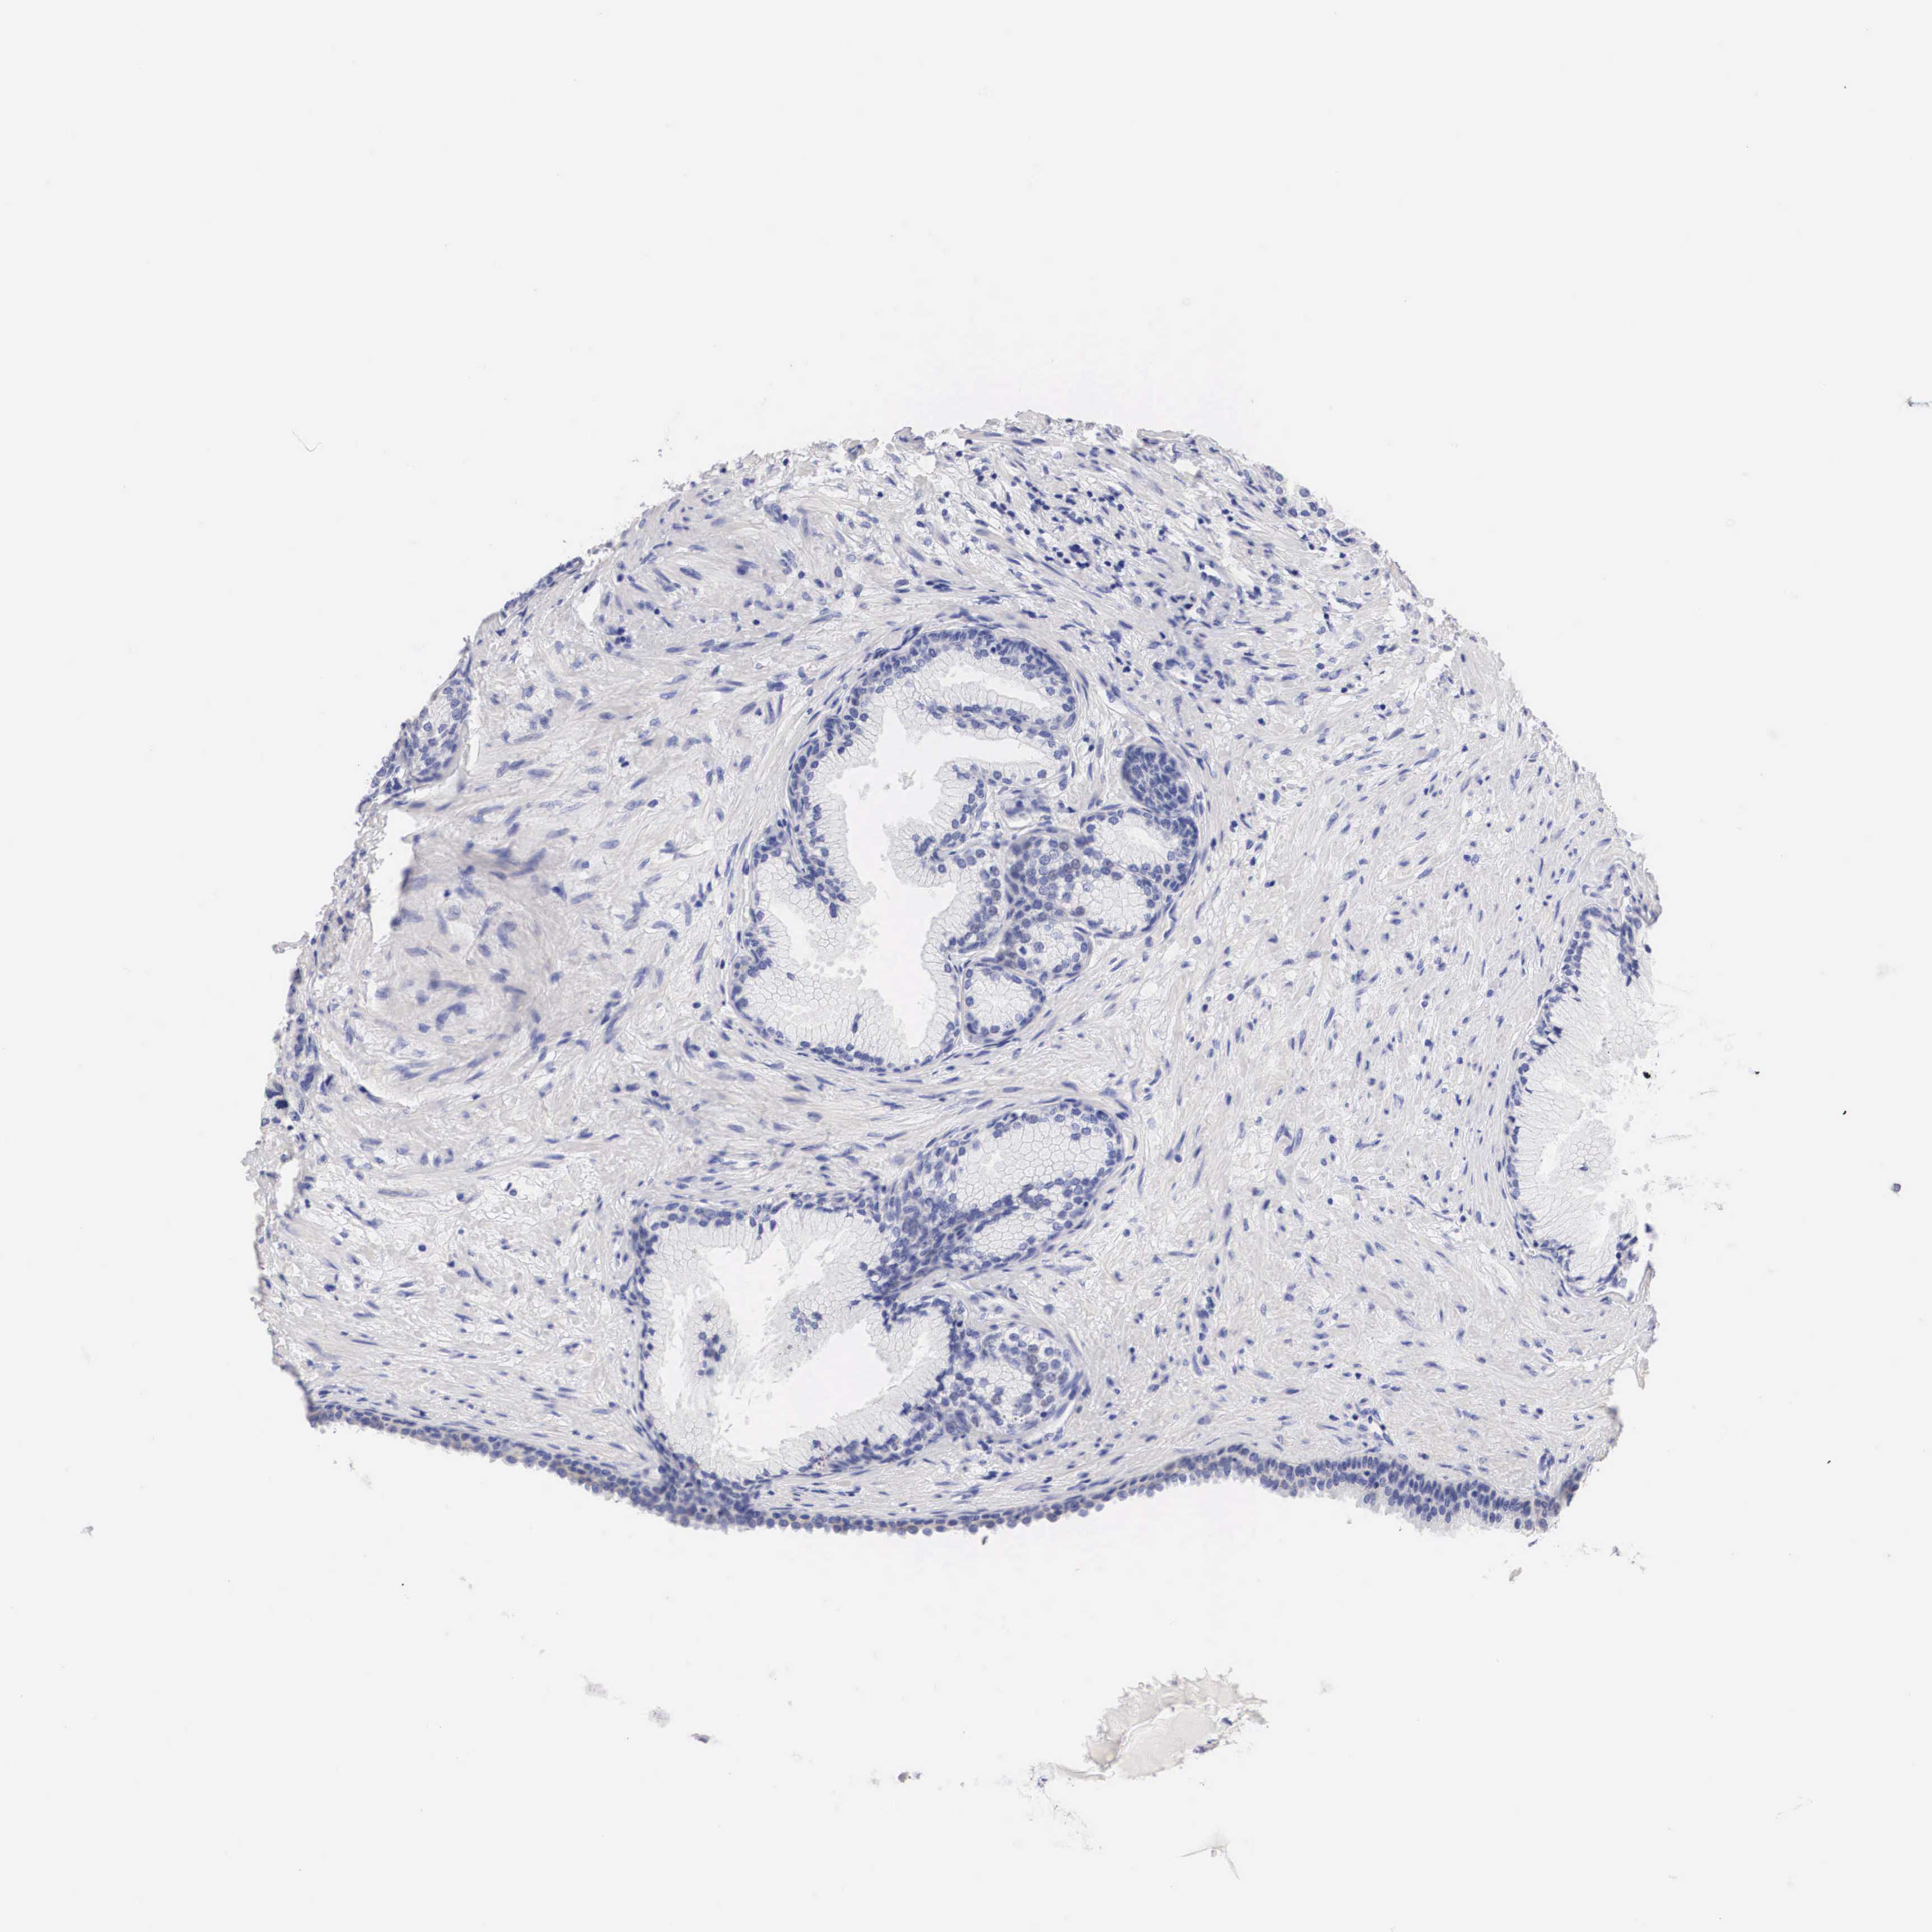

PROSTATE CANCER - Protein expressioni

A mouse-over function shows sample information and annotation data. Click on an image to view it in a full screen mode. Samples can be filtered based on level of antibody staining by selecting one or several of the following categories: high, medium, low and not detected. The assay and annotation is described here.

Note that samples used for immunohistochemistry by the Human Protein Atlas do not correspond to samples in the TCGA dataset.

Antibody stainingi

Antibody staining in the annotated cell types in the current human tissue is reported as not detected, low, medium, or high, based on conventional immunohistochemistry profiling in selected tissues. This score is based on the combination of the staining intensity and fraction of stained cells.

Each image is clickable and will lead to virtual microscopy that enables deeper exploration of all samples and also displays staining intensity scores, fraction scores and subcellular localization as well as patient and tissue information for each sample.

Antibody HPA001383

Antibody CAB000043

Antibody CAB020416

Antibody CAB062555

Adenocarcinoma, Medium grade

Adenocarcinoma, Low grade

Adenocarcinoma, High grade

Adenocarcinoma, NOS